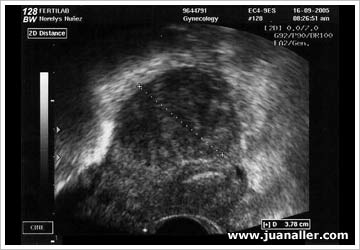

WAB 14-2: ECOGRAFÍA - ÚTERO

Mioma  intramural